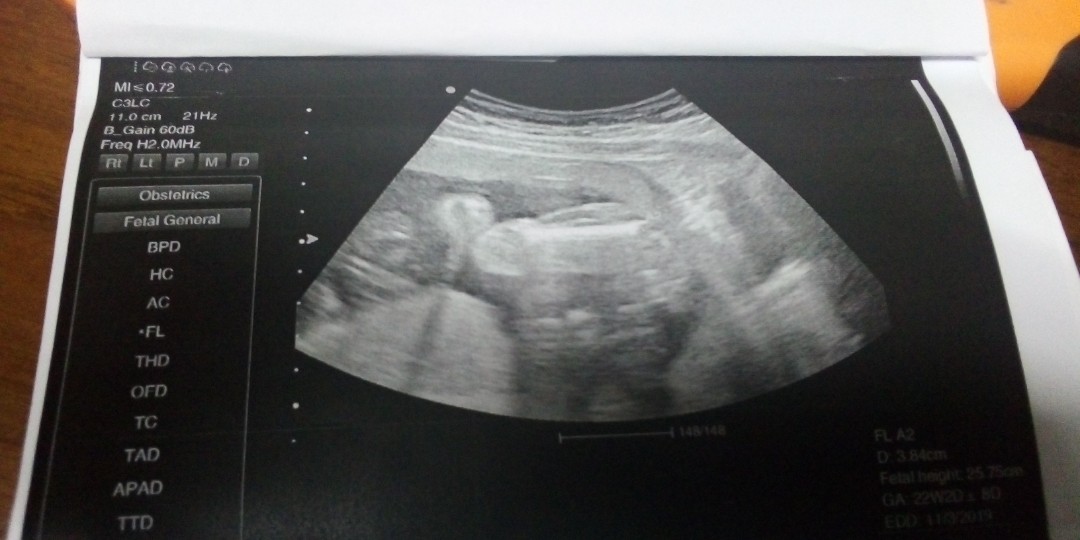

มาเป็นลำ🤣👶🏻

ไข่มาเป็นพวง😁😁😁